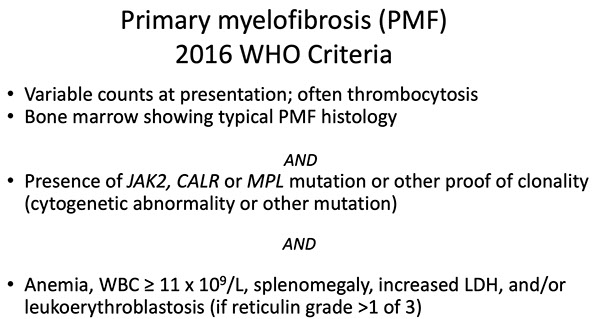

PMF

Primary Myelofibrosis

Primary Myelofibrosis (PMF)

Challenges of diagnosis PMF[2]:

- in fibrotic phases of disease, must distinguish from other causes of bone marrow fibrosis

-- close attention to morphology and mutation status (JAK2/MPL/CALR) is helpful

- in early phases of disease, fibrosis is minimal or absent

- correct diagnosis is important, since early PMF has a high risk of progression to a fibrotic disease phase and has worse prognosis than other MPNs

- morphologically distinct from ET; erythrocytosis is absent

-- increased bone marrow cellularity and more frequent, clustered megakaryocytes in early PMF compared to ET

Dx Criteria (need all 3 major and 2 minor):

Major

1.) Mkc prolif + atypia, c fibrosis (if no fibrosis, then need hypercellular BM)

2.) No PV, BCR-ABL1 CML, MDS or other neoplasm

3.) (+) JAK2 V617F or other marker (ie MPL W515K/L)

Minor

1.) Leukoerythroblastosis 2.) Inc serum LDH 3.) Anemia 4.)S-megaly